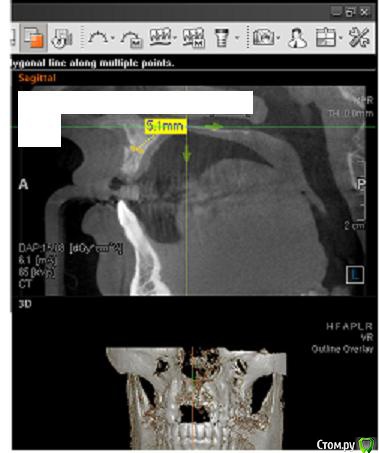

Сестричка Опубликовано 2 марта, 2015 Автор Поделиться Опубликовано 2 марта, 2015 Еще пара срезов Ссылка на комментарий

SDC Опубликовано 2 марта, 2015 Поделиться Опубликовано 2 марта, 2015 Интересны размеры беззубого альвеолярного отростка на самой вершине его или рядом с вершиной на расстоянии 1 мм. от нее в проекции будущего местоположения имплантатов.Желательно размеры проводить рядом с объектом (как в черчении)По-моему, диаметр 3 мм. подходит для имплантации без костной пластики, но без трансплантации десны, одномоментно с имплантацией, не обойтись. 1 Ссылка на комментарий

Сестричка Опубликовано 2 марта, 2015 Автор Поделиться Опубликовано 2 марта, 2015 Интересны размеры беззубого альвеолярного отростка на самой вершине его или рядом с вершиной на расстоянии 1 мм. от нее в проекции будущего местоположения имплантатов.Желательно размеры проводить рядом с объектом (как в черчении)По-моему, диаметр 3 мм. подходит для имплантации без костной пластики, но без трансплантации десны, одномоментно с имплантацией, не обойтись.Простите безграмотную, совсем не понимаю что это за отросток и где он находится(( А размеры программа автоматически куда-то уводит, я их хотела поставить как надо, не получается. Про десну понятно, что надо все сразу делать, хирург говорил, у меня дефецит десны и келлоидные шрамы от резекций. Поэтому и предлагал материал для увеличения объема десны, но я конечно тоже больше хотела бы, чтоб взяли с неба. Ссылка на комментарий